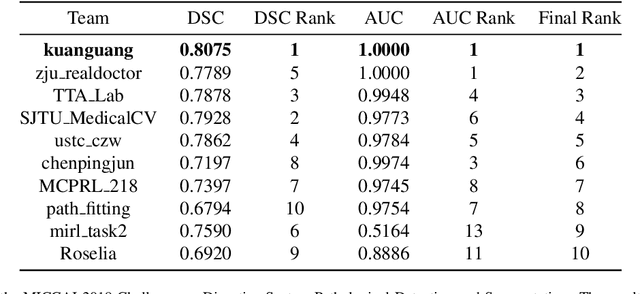

End-to-end Prostate Cancer Detection in bpMRI via 3D CNNs: Effect of Attention Mechanisms, Clinical Priori and Decoupled False Positive Reduction

We present a novel multi-stage 3D computer-aided detection and diagnosis (CAD) model for automated localization of clinically significant prostate cancer (csPCa) in bi-parametric MR imaging (bpMRI). Deep attention mechanisms drive its detection network, targeting multi-resolution, salient structures and highly discriminative feature dimensions, in order to accurately identify csPCa lesions from indolent cancer and the wide range of benign pathology that can afflict the prostate gland. In parallel, a decoupled residual classifier is used to achieve consistent false positive reduction, without sacrificing high sensitivity or computational efficiency. Furthermore, a probabilistic anatomical prior, which captures the spatial prevalence of csPCa as well as its zonal distinction, is computed and encoded into the CNN architecture to guide model generalization with domain-specific clinical knowledge. For 486 institutional testing scans, the 3D CAD system achieves $83.69\pm5.22\%$ and $93.19\pm2.96\%$ detection sensitivity at 0.50 and 1.46 false positive(s) per patient, respectively, along with $0.882$ AUROC in patient-based diagnosis $-$significantly outperforming four state-of-the-art baseline architectures (U-SEResNet, UNet++, nnU-Net, Attention U-Net) from recent literature. For 296 external testing scans, the ensembled CAD system shares moderate agreement with a consensus of expert radiologists ($76.69\%$; $kappa=0.511$) and independent pathologists ($81.08\%$; $kappa=0.559$); demonstrating strong generalization to histologically-confirmed malignancies, despite using 1950 training-validation cases with radiologically-estimated annotations only.